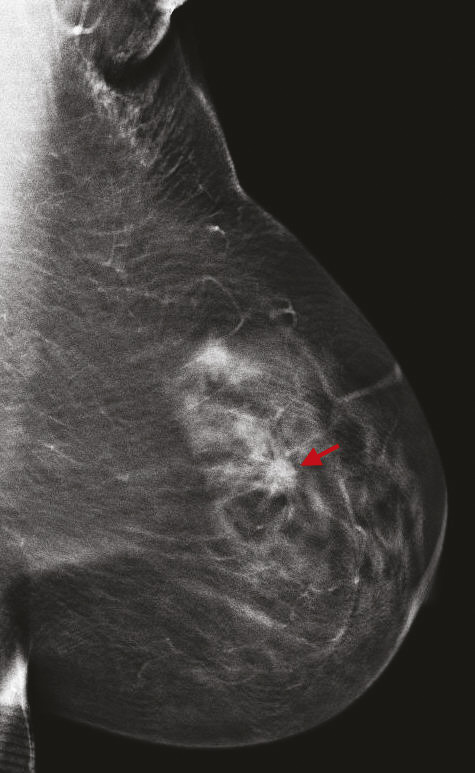

La tomosynthèse est une technique de mammographie développée depuis plus de 15 ans qui consiste non plus à acquérir deux images fixes du sein, mais un volume d’images, par un déplacement du tube de rayons X sur une angulation définie. Ainsi, le nombre d’images varie selon l’épaisseur du sein. L’avantage de cette technique est de s’affranchir d’une partie des effets masquants du tissu mammaire sur d’éventuelles lésions, et de mieux définir les contours des lésions bénignes et des cancers.

Cette technique permet d’augmenter le taux de détection des cancers, principalement invasifs, en particulier dans les seins denses de type C. Une récente étude prospective italienne a montré que la tomosynthèse mammaire deux incidences (face, oblique), associée à la vue synthétique (image 2D reconstruite à partir du volume 3D), permettait d’augmenter significativement le taux de cancers.8 Dans cette étude, 16 666 femmes asymptomatiques âgées de 50 à 69 ans ont été dépistées dans le programme de dépistage de Vérone avec une tomosynthèse deux incidences, comportant une analyse complémentaire de la vue synthétique. Les résultats ont été comparés à ceux de la précédente cohorte de dépistage de 2014, où les mammographies avaient été acquises uniquement en 2D (14 443 femmes).9 Le programme avec tomosynthèse et vue synthétique a permis une augmentation de détection de cancers invasifs significatifs par rapport au programme de dépistage 2D, avec un taux de détection de 9,30 versus 5,41 cancers pour 1 000 femmes. Ce qui est intéressant est que les cancers dépistés étaient plus souvent des cancers invasifs de stade 1 (72,3 % avec la tomosynthèse vs 50 % avec la mammographie 2D), avec moins de cancers in situ (9 % avec la tomosynthèse vs 26,9 % avec la mammographie 2D). Le taux de rappel était similaire entre les deux techniques (4 % pour la tomosynthèse vs 4,2 % pour la mammographie 2D). Ces résultats sont en accord avec les principales études prospectives et rétrospectives comparant l’apport de la tomosynthèse par rapport à la mammographie 2D.10 11